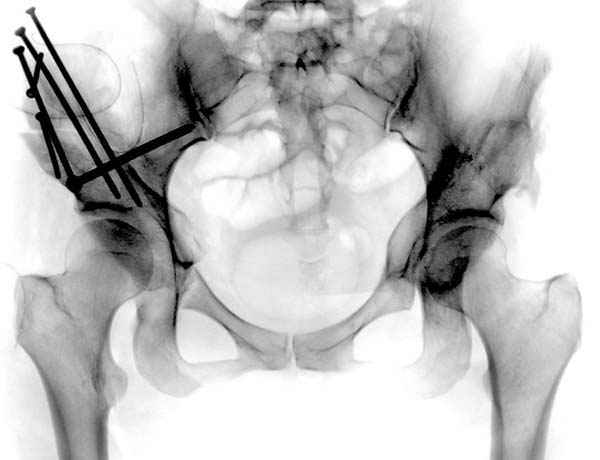

Модель несовершенна, согласен, однако я экспериментировал и с импровизированной илеофеморальной связкой и ацетабулярной губой. Результат был тот же, подвижный узел замыкался посредством аналога СГБ. Для интереса я прилагаю фото., где сымитированы наружные связки и вертлужная губа, но без СГБ видно по показаниям динамометра, что данные структуры незначительно только на 0.5 кг разгружают аналог отводящих мышц. Почему модель получилась именно такой можно рассказать и подробнее если захотите…